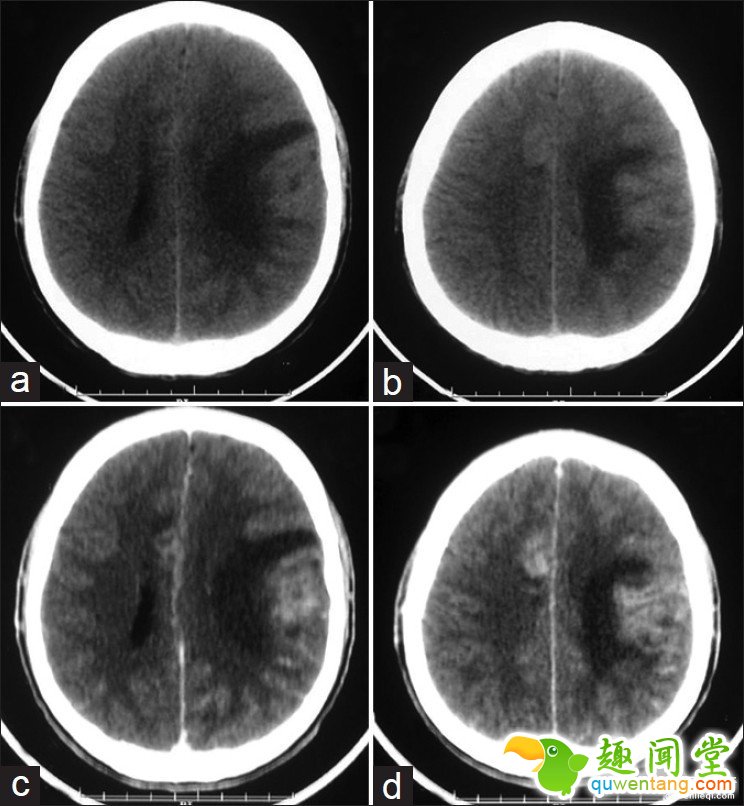

说是食脑虫,但其实阿米巴原虫并不以人脑为食。它们的存在本身,在大脑内引发了严重出血和脓肿,并造成脑内水肿,颅压上升,最终导致脑神经瘫痪。这才是令患者致死的真正原因。